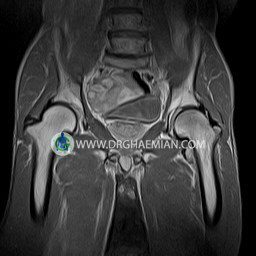

پزشکان اغلب از تصویربرداری ام آر آی برای تشخیص و درمان عارضه های پزشکی که فقط با استفاده از اشعه ایکس یا میدان مغناطیسی و امواج رادیویی قابل مشاهده است، استفاده می کنند. دستگاه ام آر آی تصاویر دقیق از ساختار های داخلی بدن ایجاد می کند. در این کیس استئومیلیت لگن، آتروز و سنیویت دیده می شود.

HIP JOINT MRI

( without contrast )

Technique : coronal STIR , coronal T2 , Axial T1 , axial T2 .

REPORT:

The femoral heads and acetabula are normal shape , signal intensity and the femoral heads are well covered by the acetabular margins .

The joint spaces are of normal width without fluid collection .

The articular surfaces are smooth and congruent and show normal cortical thickness .

Each femoral shaft has normal margins and contains a normal bone marrow signal .

The imaged muscles and the lesser pelvis show no abnormalities .

– Heterogeneous signal change (high T2/STIR , low T1) in proximal metaepiphysis of left femur without articular surface irregularity suggestive for bone bruise (stress fracture?), osteomyelitis & arthritis and marrow infiltration (less probable)

– Left hip joint effusion suggestive for synovitis

are seen.

COMMENT: Clinical correlation and MRI with contrast are recommended.